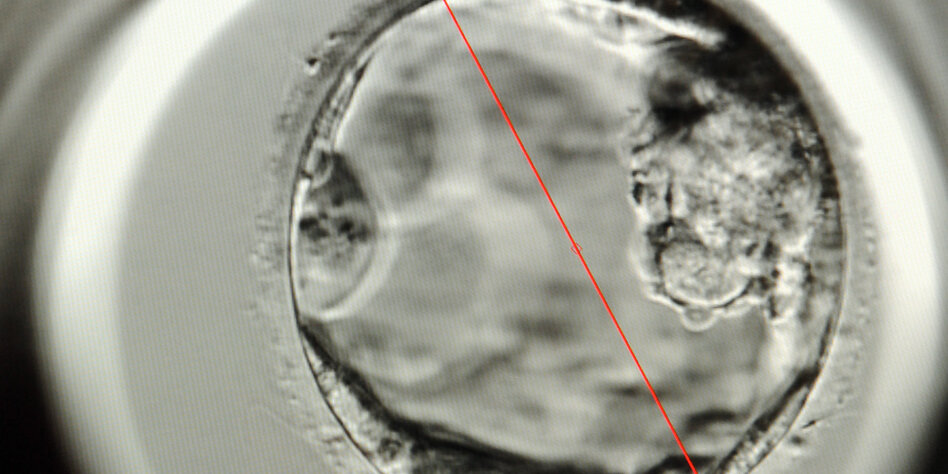

(IMG) Bild: Ein fünf Tage alter Embryo – rechts neben der roten Linie.